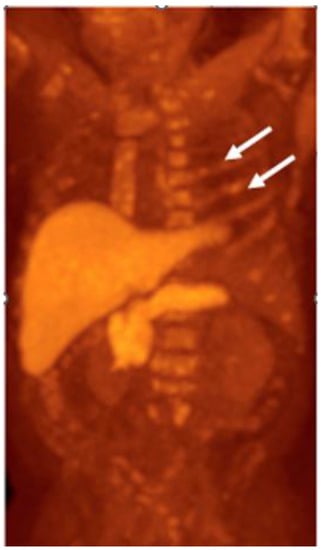

Detection of Loco-Regional Disease and Distant Metastases